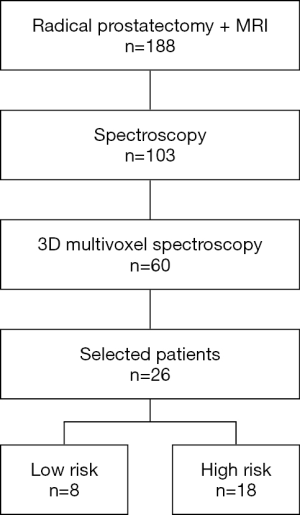

We retrospectively reviewed the clinical and imaging data of all patients who had radical prostatectomy after mp-MRI examination combined with NMR-S between 2009 and 2016 (Figure 1). The study was approved by institutional ethics board of Dijon University Hospital and individual consent for this retrospective analysis was waived. The data were collected and reviewed by an expert radiologist, a senior prostate cancer expert, and a junior urologist. There were no exclusion criteria except T2-weighted (T2w) sequences that did not show obvious tumor according to the radiologist.

Of 182 patients treated by prostatectomy after undergoing MRI in our institution, 103 also underwent spectroscopy, including 60 who underwent 3D multivoxel spectroscopy. We selected 26 patients whose T2w imaging sequences showed an obvious tumor identified by the expert radiologist (Figure 3). These sequences were then reviewed again by a senior doctor specialized in spectroscopy and by a junior doctor not specialized in imaging, in order to select the slices to be analyzed, on which regions of interest (ROIs) containing both tumor and healthy areas were traced.